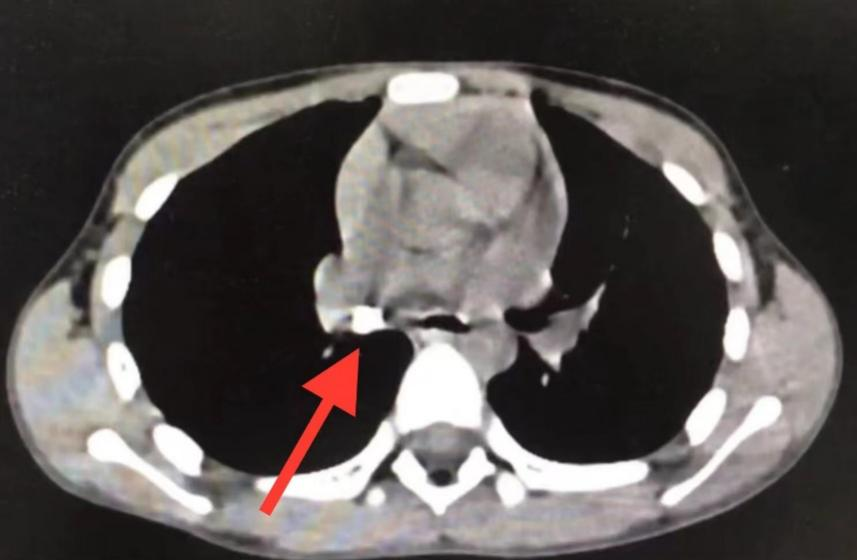

慢阻肺您了解吗?